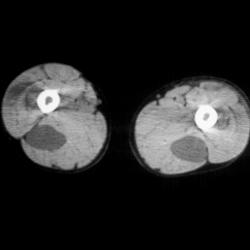

Osteomyelitis